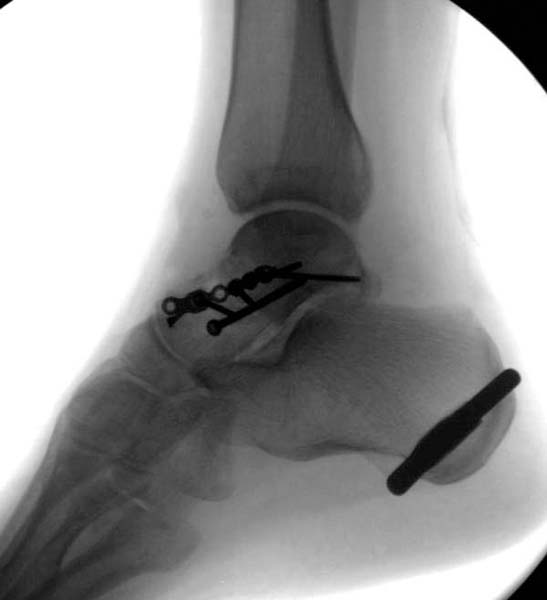

Больная стабильная после хирургических мероприятии и получив добро, приступили к закрытому вправлению таранной кости с укладкой наружного фиксатора. Затем укладка больную на бок и открытый остеосинтез перелома-вывиха головки бедра.

После спадения отека на стопе произведена фиксация тарана. Кстати, коллеги пересмотрели первоначальную консультацию по позвоночнику и на двух уровнях провели фиксацию. Из-за длительного постельного режима без нагрузки таз не стали оперировать...